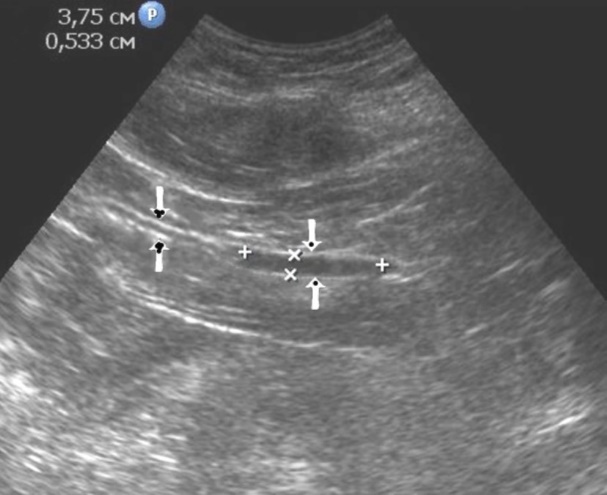

The polypoid type of gastric cancer was observed in 3 (4,9±2,8%) cases, the ulcerative type – in 18 (29,5±5,8%), the infiltrative ulcerative type – in 27 (44,3±6,4%) and the diffuse infiltrative type – in 13 (21,3%±5,2%) cases respectively (Table 2). On the echogram, the tumor was

Visualized as a polypoid formation on a wide base above the gastric mucosa of a non-uniform structure, an irregular surface (Figure 5, Figure 6, Figure 7).

Figure 5.The polypoid type of gastric carcinomas for T3 stage. On the posterior wall of the antrum, a polypoid formation with a fuzzy contour is visualized, the image of the mucous and serous membranes (arrows) is discontinuous.

Figure 6.The gastric carcinoma for T3 stage. The tumor is visualized as a polypoid formation on a wide base above the gastric mucosa of a non-uniform structure, an irregular surface (arrows).